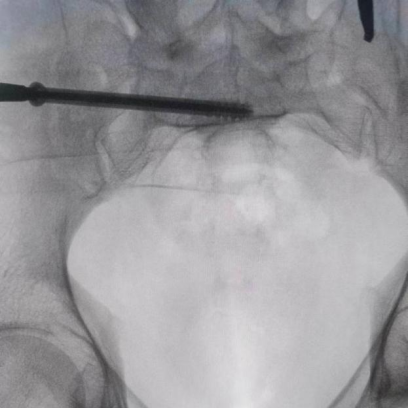

據(jù)了解,患者37歲,為高墜傷患者,入院合并顱腦挫傷、盆腔臟器出血、骨盆骨折多發(fā)傷患者。為最大限度降低手術(shù)風(fēng)險,同時給予患者滿意的手術(shù)療效,術(shù)前綜合評估患者病情,擬定行“天璣機器人”輔助定位下骨盆骨折微創(chuàng)手術(shù)。2月13日10時,手術(shù)正式開始。拉薩市人民醫(yī)院采集患者術(shù)中二維影像,通過骨科手術(shù)機器人擬定螺釘打入位置方向后,吳宏華主任完成手術(shù)設(shè)計,成功為該患者置入了一顆高難度骶髂螺釘,出血5ml,切口1cm。術(shù)后圖像顯示,螺釘位置及方向完全符合手術(shù)規(guī)劃,沒有一絲偏差,手術(shù)最終獲得圓滿成功。

圖為透視下見置入的骶髂螺釘,位置、長度精準,無絲毫偏差